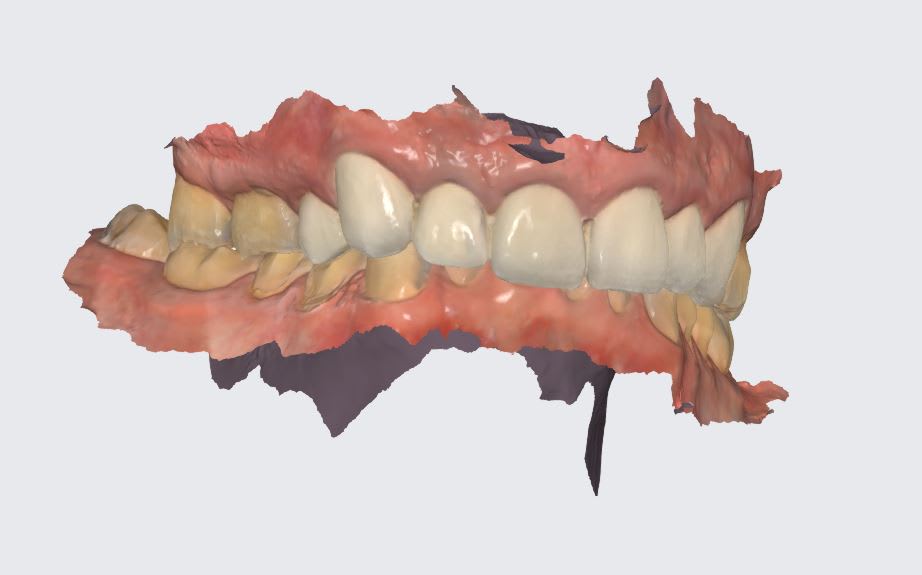

Bon, américain de 70 ans, ressemble à Castex, donc la bombasse j'ai pas sous la main, usure étrange à 60° maxillaire palatine sur les molaires. Vient 15 jours, a pas les moyens de se faire traiter aux USA, ne demande pas la lune mais de pouvoir mâcher des burger sans avoir mal. je me demande si une restauration postérieure peut faire l'affaire, suis tellement étonné de la forme de l'usure des mol maxillaires.

Wakrap , ton Américain a un sur guidage ant avec en plus un sur-contact cingulaire en fin de mvt de fermeture .

ce qui fait qu il se retrouve avec une oim en arrière de sa centrée , à tous les coups .

si tu veux reconstruire derrière , il faut lui donner de l espace devant , donc refaire le bloc ant , puisque je vois que tu es déjà sur le métal .

quand tu es comprimé des atm , il faut que tu te trouves du jeux pour te détendre un petit peu , et ce jeux , il l a trouvé en fracassant les molaires ce qui lui permet d avoir une liberté droite gauche .

en gros le jeux antero post qu il a perdu , il l a compensé en se créant un jeux latéral .

Parce que ça n’y ressemble pas ici tout simplement. T’as déjà tout résumé: classe 2, bloqué par la palissade de CCM antérieur, effondrement de la DVO évidente.

Radio des ATM (l’IRM risque d’être impossible dans les îles) va montrer des condyles enfoncés en postérieur= irritation zone bilaminaire= douleur tragus interne et palpation des pterygidiens douloureuse. Bin voilà on l’a trouvé notre client 3 Step ;-)

Les attaques acides laissent systématiquement des traces jaunes-orangés sur les tissus dentaires. Les 7 seraient plus atteintes que les 6, et il y aurait une attaque en lingual des inf. Ici le bas est bouffé en vestibulaire et le haut en palatin, leur usure est mécanique: effondrement DVO chez CL2 qu’on a enfermé en antérieur. Voir aussi si on a pas une langue en position reculée et une tendance au SAHOS…..,mais pas régurgitation acide:vomissements,

25,26 et 27 sont niquées de la même façon en palatin. Et la perte de substance va jusqu'en sous gingival. Si c'était mécanique, il se boufferait aussi la gencive.

M'étonnerait pas qu'il ait une langue énorme qui recouvre ses dents inférieures et qui les protège, tout en gardant le reflux acide au contact des dents maxillaires mais bon là je m'égare peut-être..